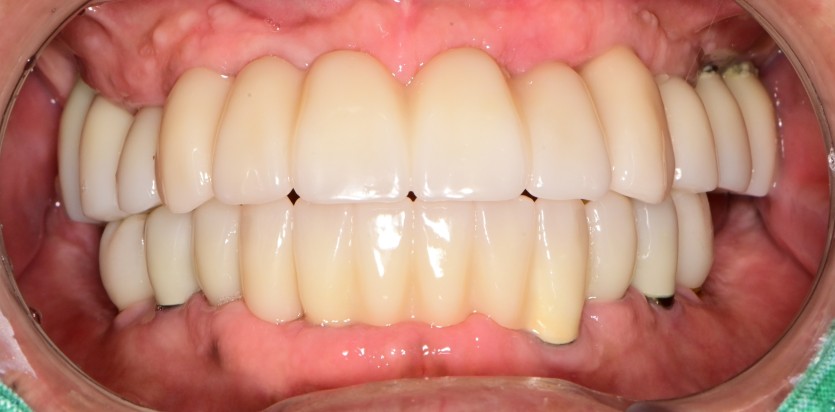

만 58세 전체 임플란트 증례

전체 임플란트 증례입니다.

16개의 임플란트로 완성하였습니다.